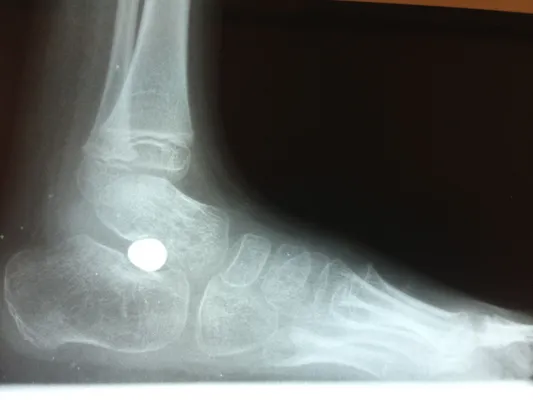

Pre-operative x-rays of the flatfoot with the talus deviated medially due to subluxing off the calcaneus causing the midtarsal joint to sublux laterally and uncovering of the talar head at the talo-navicular joint (left). The talus bone should line up with or be close to paralletl with a line drawn through the 1st metatarsal shaft (right). This is referred to as Meary's angle.

One case see an improvement in Meary's angle after surgical repair of the flatfoot with a subtalar joint implant which blocks the subluxation of the talus off of the calcaneus.

Below are x-rays of a foot pre-operatively (left) where the black line indicates and plantarflexed (downward directed) talus bone and post-surgical repair with a subtalar joint implant and lenthening of the calf muscle which allows the calcaneus (heel bone) to set underneath the talus and the implant keeps the talus from subluxing off the calcaneus and now the talus is more inline with the front of the foot (right).